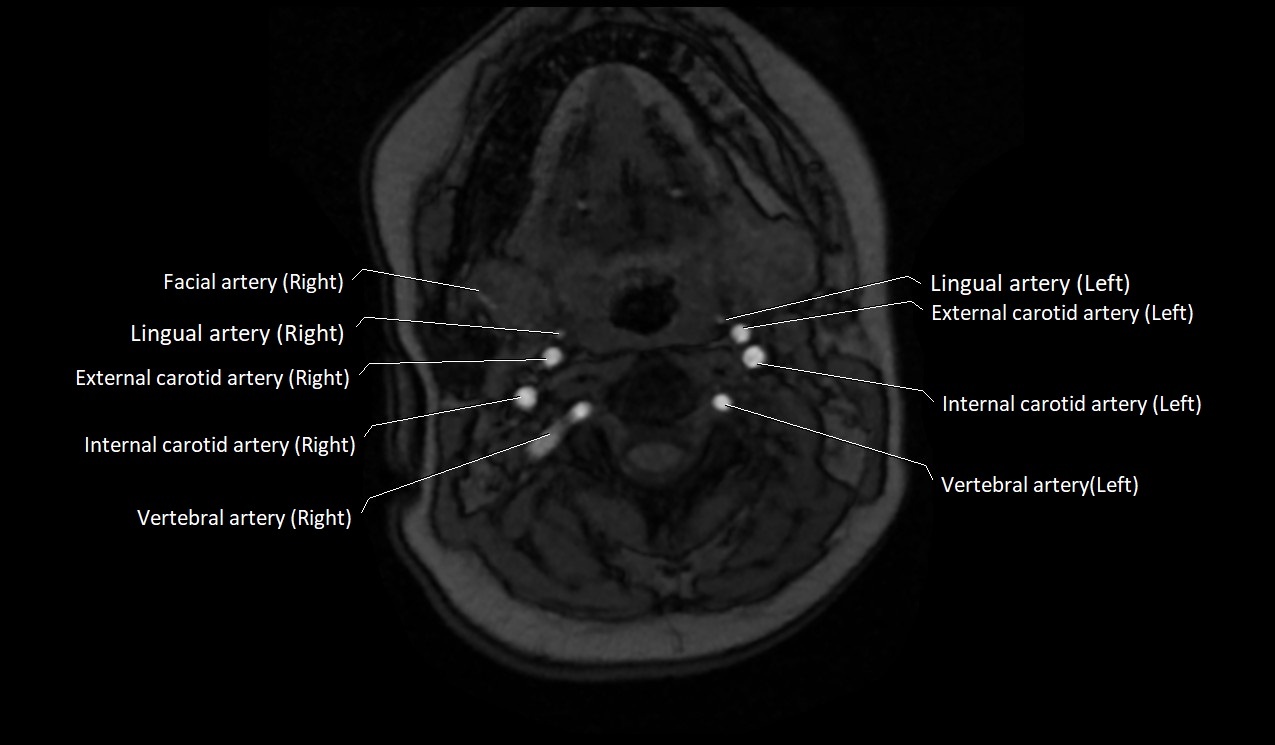

CT image

image